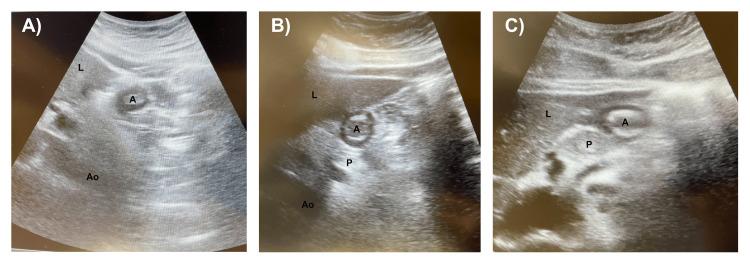

Introduction Glucagon-like peptide-1 receptor agonists (GLP1-RAs) are used in the treatment of type 2 diabetes mellitus and obesity. A side effect of GLP1-RAs is delayed gastric emptying, which could increase the risk of pulmonary aspiration. This exploratory pilot study examines the use of ultrasound to identify high-risk patients taking GLP-1RAs before elective surgery. Methods A prospective study from July 2023 to February 2024 was conducted on patients who took their last weekly dose of semaglutide less than seven days before surgery. If preoperative gastric ultrasound revealed an empty stomach, surgery proceeded. Patients with residual gastric contents were rescheduled. Patient demographics, semaglutide dosage and timing, nil per os (NPO) time, and postoperative complications were reviewed. Statistical significance was set at p < 0.05. Results Twenty-five patients took their weekly semaglutide less than seven days before surgery. Twenty patients (80%) demonstrated empty stomachs on ultrasound and proceeded with surgery without complications. Gastric contents were found in five patients (20%), and surgery was rescheduled. Patients who took semaglutide one to three days before surgery were more likely to have residual gastric contents as compared to those who took semaglutide four to six days before surgery (p = 0.02). Discussion Gastric ultrasound is a useful tool that can prevent the cancellation of surgery for patients on semaglutide. Patients who took semaglutide within one to three days were more likely to have residual gastric contents compared to those who took it four to six days prior. Conclusion Preoperative gastric ultrasound can identify high-risk patients on semaglutide despite adequate NPO status.